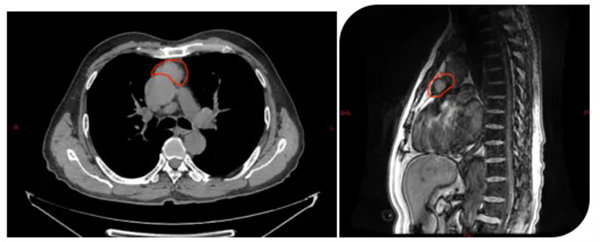

該患者體檢時胸部CT發現前上縱隔見團塊狀高密度影,范圍約3.6cmX3.2cmX24cm,鄰近心包局部凹陷,考慮胸腺瘤。胸外腫瘤外科主任陳瑜率領團隊仔細閱片并討論后確認腫瘤與心包關系緊密,進一步胸部磁共振檢查后明確心包存在侵犯,考慮侵襲胸腺瘤,手術指征明確。